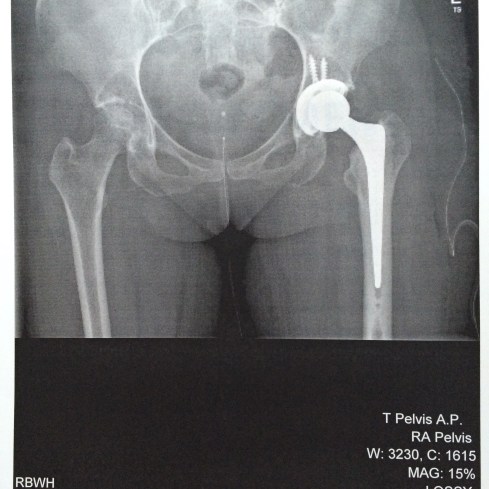

And this my friends, is my new left hip!

Incredible isn’t it?

This x-ray also shows a deterioration of the bone in my right hip, in line with the early stage Avascular Necrosis reported in the MRI a few weeks back.